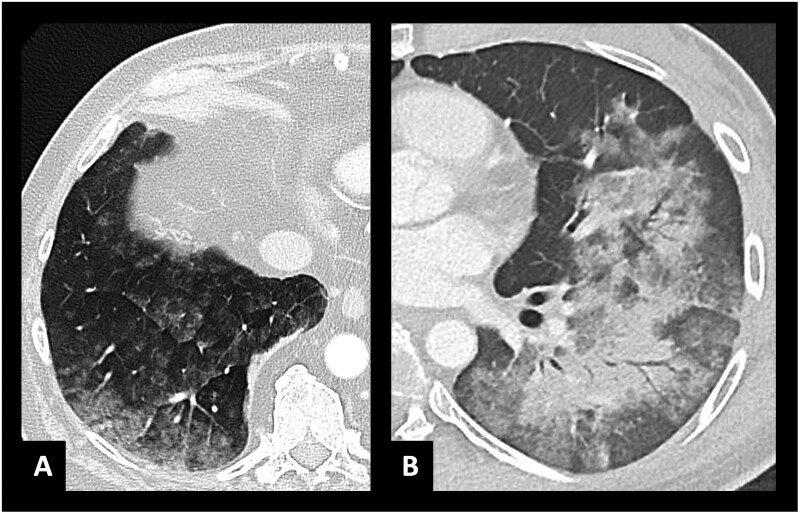

Abstract Image